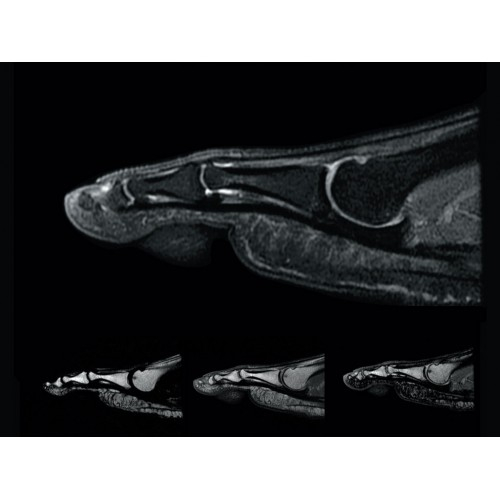

• РЧ-катушки, оптимизированные для исследования конкретных участков тела — элементы катушек высокой плотности располагаются вокруг исследуемых участков тела и при необходимости обеспечивают расширенный охват и оптимальное качество изображений при каждой процедуре.

• Широкое поле зрения — поле зрения шириной 50 см позволяет охватывать крупные анатомические области за меньшее число сканов.

• Радиологам достаются изображения великолепного качества, необходимые им для постановки точных диагнозов.